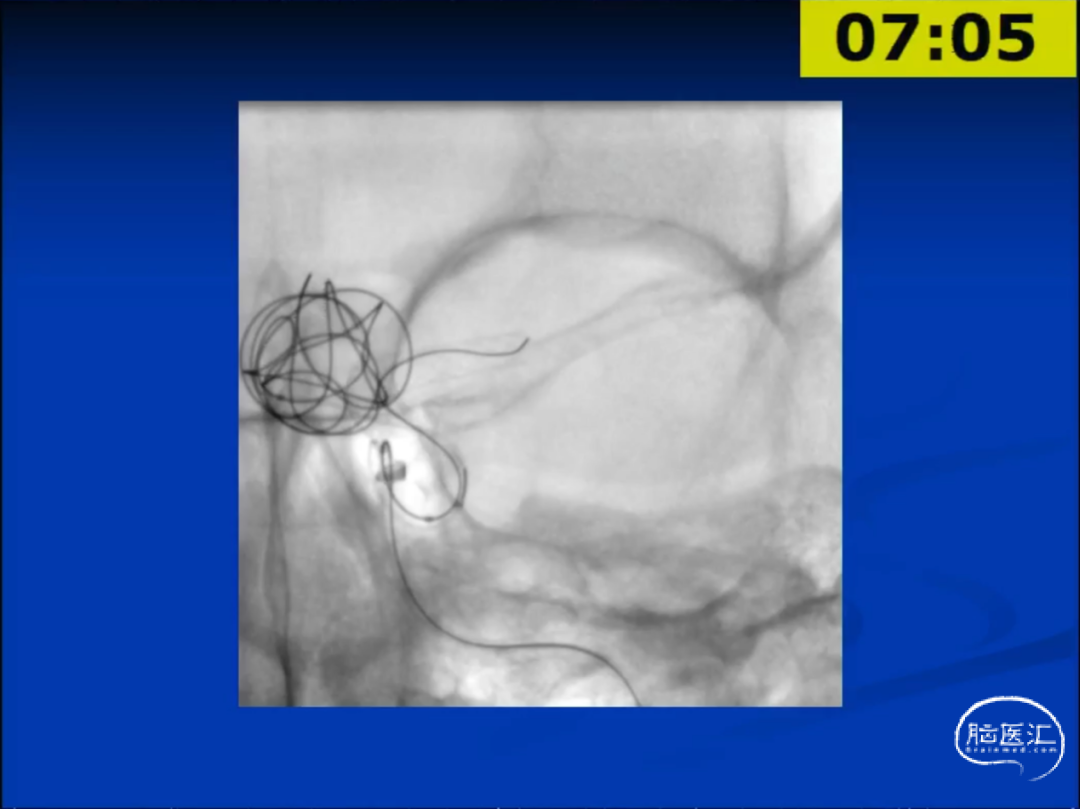

鉴于两种技术的各自优势,临床上对于某些病例选择联合使用FD和弹簧圈是可行的。举例说明:19岁男性,头痛数月,无神经定位体征,检查发现左侧颈内动脉床突段巨大动脉瘤。

术中使用了微导管及7×7mm球囊导管,置入一枚5×35mm的FD。

然而,6个月后的造影复查,发现动脉瘤没有完全闭塞,这是由于动脉瘤瘤体发出粗大的后交通动脉。第二次手术,选择了经后循环-后交通动脉的颈内动脉动脉瘤弹簧圈栓塞术。此次术后该患者的动脉瘤得到了完整闭塞。